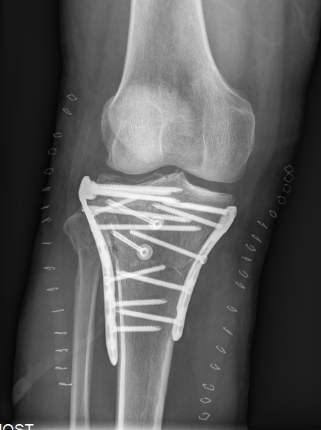

4、图8-9 术后X片见骨折复位及内固定满意